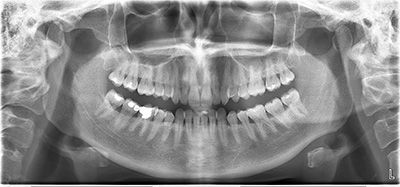

Ортопантомография — это стоматологическое рентгенографическое исследование, которое позволяет сделать панорамный снимок верхней и нижней челюсти для передачи на пленку или компьютер. Исследование позволяет диагностировать большинство стоматологических заболеваний, оно позволяет визуализировать мягкие и твердые ткани зуба, пазухи, челюсть. Для панорамного снимка используется аппарат — ортопантомограф.

Ортопантомограмма — это обзорный рентгеновский снимок челюстей, на котором можно рассмотреть верхнюю и нижнюю челюсть, все зубы и лунки, особенности пломб, строения височно-нижнечелюстного сустава и всех мягких тканей. Современную стоматологию трудно представить без этого обследования, ставшего международным стандартом.

Подробное изучение снимка может дать врачу важную информацию и позволяет оценить:

- строение челюстей;

- строение и изменения височно-нижнечелюстных суставов;

- зубные ряды;

- соотношение всех структур с гайморовой пазухой и нервом нижней челюсти;

- состояние пломб;

- качество пломбировки каналов;

- состояние тканей пародонта;

- состояние костной ткани после удаления зуба;

- состояние костных лунок при пародонтозе;

- выявить опухоли, кисты и участки резорбции кости;

- не прорезавшиеся и неправильно расположенные зубы;

- выявить скрытый кариес;

- выявить детали, которые невозможно обнаружить другими методами исследования.

Ортопантомография (сокращенно ОПТГ) — лучший метод диагностики при лечении, удалении и протезировании зубов. Незаменимые сведения дает этот метод при имплантации зубов, при составлении плана восстановления зубного ряда.